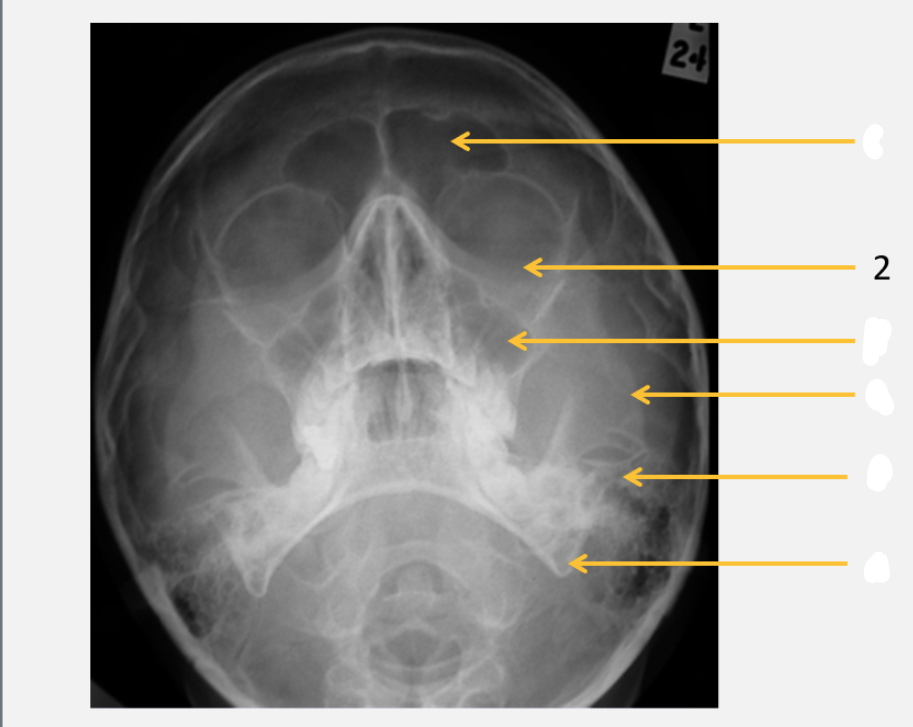

frontal bone

frontal sinus

parietal bone

lambdoid suture

occipital bone

mastoid air cells

Sella turcica

inferior orbital rim

maxillary sinus

zygomatic arch

petrous ridge

angle of mandible